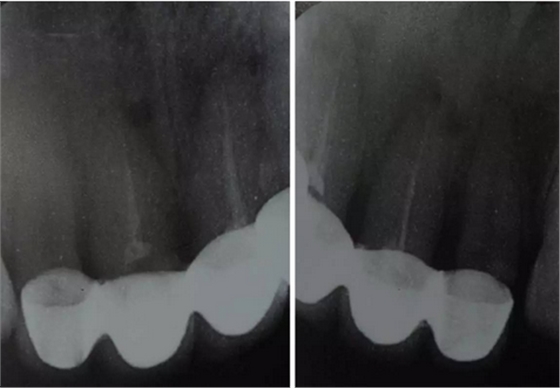

臨床檢查可見12~22烤瓷聯(lián)冠修復(fù),冠邊緣不密合,齦緣外形不協(xié)調(diào),牙齦紅腫,22烤瓷冠崩瓷。根管治療不完善,牙齦根尖部位有瘺管,X線影像顯示11、21根尖有陰影。上頜前突,上前牙修復(fù)體舌傾。 患者治療前口內(nèi)像 側(cè)位像 治療前曲面體層片 治療前前牙區(qū)X線片

董艷梅教授:修復(fù)前如有以下情況,應(yīng)考慮進(jìn)行根管再治療:① X線片顯示前次根管治療不完善;② X線片顯示患牙根尖周新增病變或根尖周病變范圍擴(kuò)大或未見縮??;③ 患牙在前次根管治療后長(zhǎng)期有癥狀或臨床體征。要明確的是,首次根管治療失敗后原則上應(yīng)首選非手術(shù)根管再治療。根尖手術(shù)原則上應(yīng)該在完成完善的根管治療后進(jìn)行。